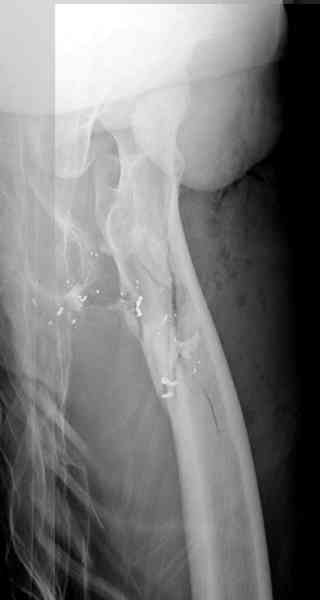

В нашем случае 21 летний боец уличного фронта, фиксацию провели на следующий день, зафиксирован интрамедуллярным штифтом. Не стали делать первичную хирургическую обработку точечной раны, зафиксирован как есть. Клинические снимки: